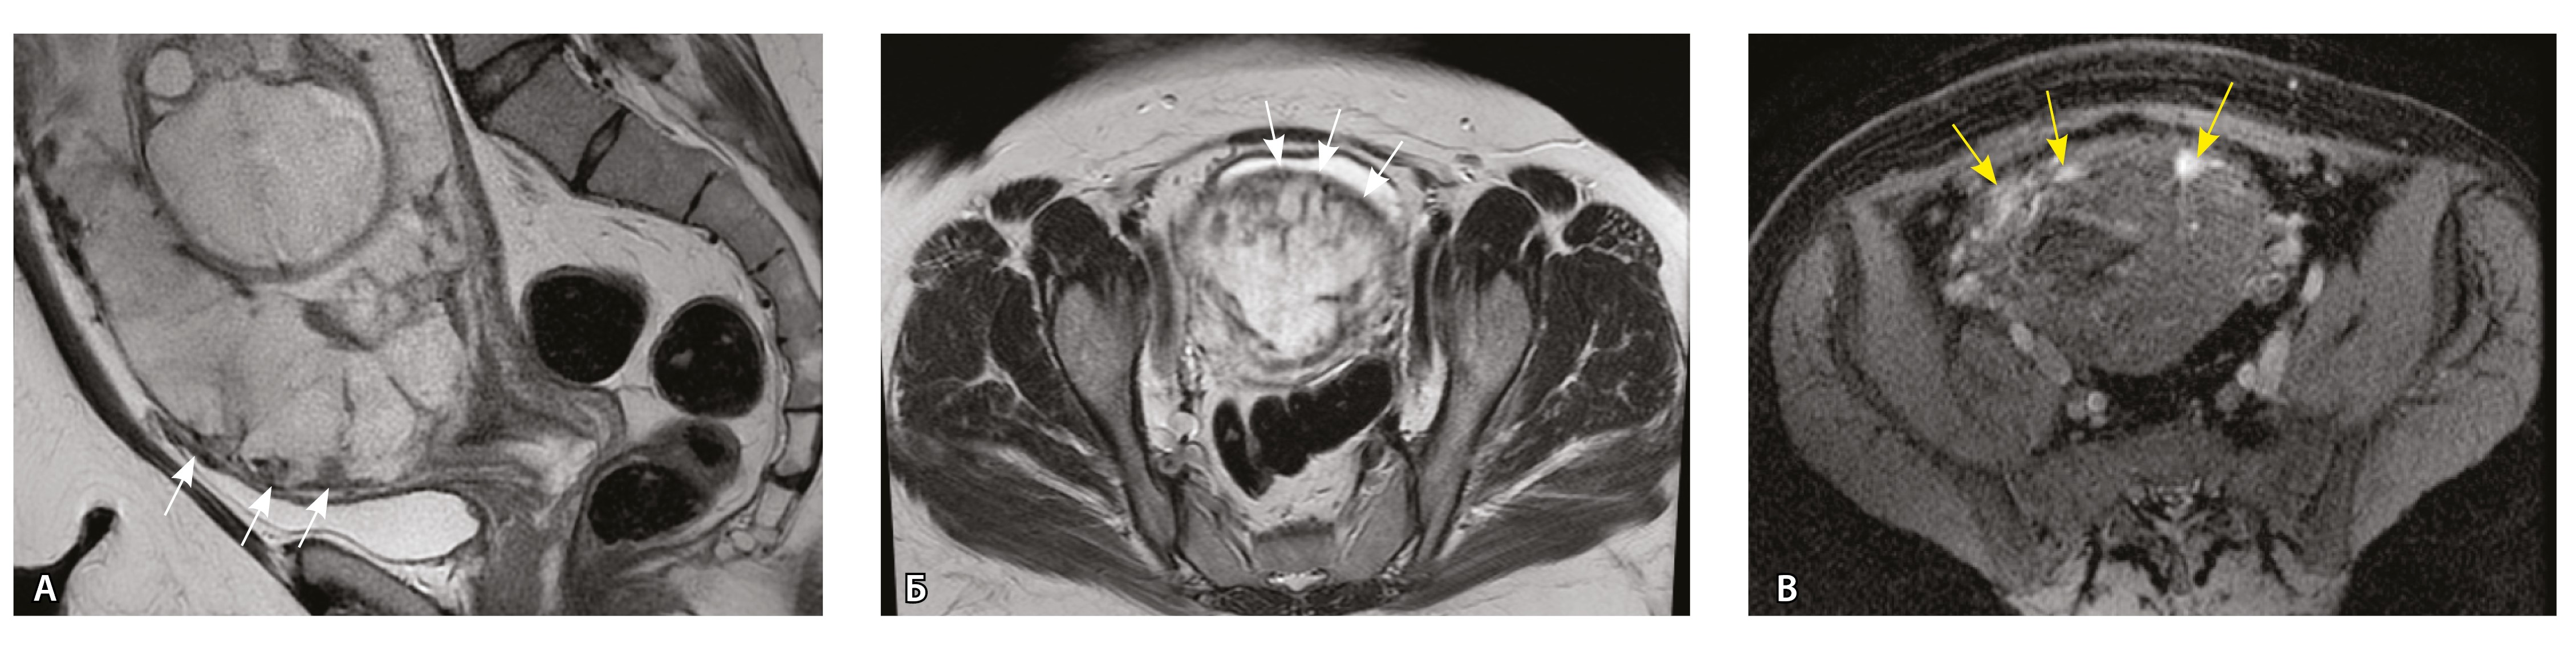

Сосуды 4-го типа. Наличие крупных извитых анастомозирующих сосудов, преимущественно по поверхности матки (в составе серозной оболочки матки) в сочетании с выраженным истончением нижнего сегмента матки (рис. 10).

Рис. 10. Беременность 33 недели, pl. percreta, PAS 3a по FIGO. На магнитно-резонансных томограммах в режиме Т2-взвешенного изображения в сагиттальной (A) и фронтальной (Б, В) плоскостях определяется внутриматочная гиперваскуляризация (желтые стрелки) и гиперваскуляризация в области выраженно истонченного нижнего маточного сегмента, с наличием многочисленных анастомозирующих сосудов по поверхности матки (белые стрелки); стенка матки в данной области представлена ретроплацентарными сосудами

Главным отличием крупных сосудов в составе серозной оболочки является то, что морфологически они находятся в пределах стенки матки. Об этом свидетельствует наличие в операционном материале тонкого поверхностного слоя мезотелия, отделяющего матку от брюшной полости (рис. 11). Его невозможно визуализировать методом МРТ из-за особенностей метода и толщины получаемых срезов.

Рис. 11. Сосуды 4-го типа при гиперваскуляризации стенки матки при патологической инвазии: А – крупный сосуд в составе серозной оболочки матки: справа видны единичные цитотрофобластические клетки (стрелки), не достигающие стенки артерии (иммуногистохимическое исследование, маркер цитокератин 8; × 50); Б – крупные сосуды в составе серозной оболочки: наличие внутреннего слоя эндотелиоцитов (иммуногистохимическое исследование, маркер СD34; × 50)

На микропрепаратах васкуляризация серозной оболочки представлена множеством крупных сосудов, идущих в разных направлениях и анастомозирующих друг с другом. Возможно, имеются артериовенозные соустья. На серийных срезах также видно, что в стенках артерий трудно различимы два слоя миоцитов (продольный и поперечный). Со стороны адвентиции они окружены толстым «футляром» из грубоволокнистой голубой ткани (при окраске по Маллори). Она проникает в стенку артерий, замещая мышечный слой (рис. 12).

Рис. 12. Истончение миометрия; в составе серозной оболочки видна крупная артерия, окруженная плотной соединительной тканью. А – cосуды в составе серозной оболочки (окраска по Маллори; × 200), не дифференцированная на мышечные оболочки стенка артерии, справа – вена, оба сосуда покрыты фиброзной оболочкой, внизу виден слой мезотелия в составе серозной оболочки; Б – серийный срез тех же сосудов при окраске на выявление эластических волокон, сосуд с соединительнотканной муфтой (окраска по Вейгерту; × 50): определяется полная дезорганизация эластичного материала в стенке; стрелкой указан мезотелий (аналог pl. increta, PAS 2 по FIGO)

Эластический каркас представлен сетью тонких волокон, без концентрации на внутреннюю и внешнюю мембраны. Однако маркер СD34 констатирует сохранение эндотелия, что свидетельствует о том, что по артериям циркулирует кровь, не сворачиваясь (рис. 13).

Рис. 13. Самые крупные сосуды в пределах серозной оболочки стенки матки: А, Б – серийные срезы артерии; × 50. При окраске по Маллори (А) видна тонкая полоска мезотелия (черная стрелка), слабо дифференцированная мышечная стенка артерии, вокруг нее – плотная коллагеновая оболочка (желтая стрелка), в просвете определяются тромботические массы. При окраске по Вейгерту (Б) наблюдается полная потеря внутренней и внешней эластических мембран

Анализ частоты встречаемости сосудов 4-го типа при различных степенях приращения плаценты (рис. 14) показал: при плотном прикреплении плаценты (gr 2) и поверхностном приращении (gr 3) сосуды данного типа не выявлены, при pl. increta (gr 4) частота встречаемости незначительная – 16,7%, а при глубокой инвазии плаценты (pl. percreta, gr 5) сосуды этого типа преобладают (р < 0,001, хи-квадрат Пирсона).